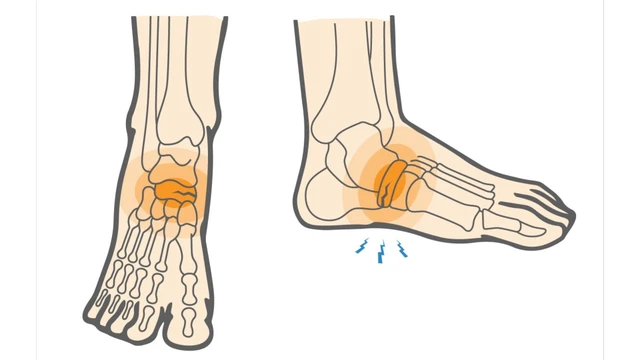

:format(webp)/ran_xuong_ban_chan_co_nguy_hiem_khong_d3ac63c9f1.jpg)

Rạn xương bàn chân là sự cố thường diễn ra đối với các vận động viên hoạt động liên tục trong thời gian dài. Đa số trường hợp đều không quá nghiêm trọng, cần người bệnh nghỉ ngơi tĩnh dưỡng sẽ bình phục trở lại. Nhưng cũng có những trường hợp cần bó bột để phục hồi tốt nhất.